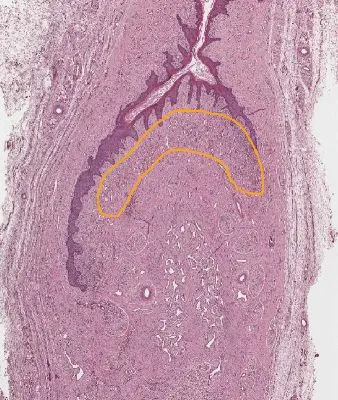

What region of the clitoris is outlined below?

{{c1::glans clitoris erectile tissue}}

Histology::Unit_8::Mid_Unit::Lab_Female_Reproductive_System